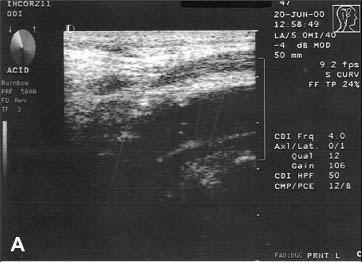

Realizou Doppler colorido de carótidas e órbitas que evidenciou: obstrução total da artéria carótida interna direita (Figura 2A), estenose estimada em 80 a 99% em artéria carótida interna esquerda, ausência de fluxo nas artérias vertebrais e fluxo reverso na artéria oftálmica direita (Figura 2B).